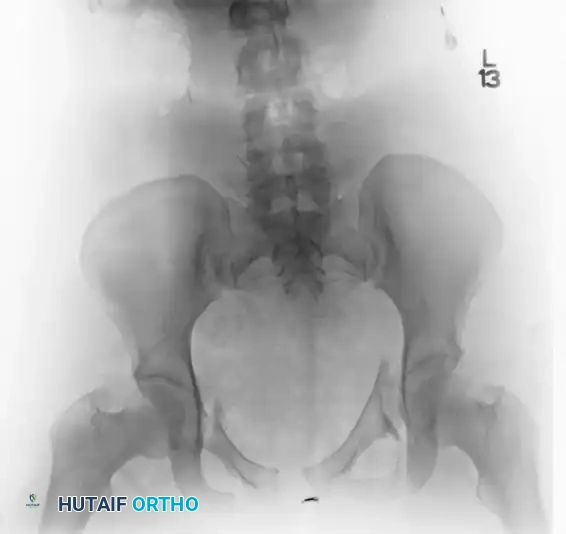

An AP III injury is a completely unstable pelvic ring disruption. It involves complete disruption of the symphysis pubis (or anterior rami) and complete disruption of both the anterior and posterior sacroiliac ligamentous complexes. The hemipelvis is both rotationally and vertically unstable.

The preoperative AP, inlet, and outlet views demonstrate severe pubic diastasis, bilateral pubic rami fractures, and gross widening/displacement of the posterior SI joints.

FIGURE 56-45: Young and Burgess anteroposterior type III (AP III) pelvic ring injury with pubic diastasis and bilateral pubic rami fractures. A-C, Preoperative anteroposterior, inlet, and outlet views, respectively. D, Preoperative CT scan.